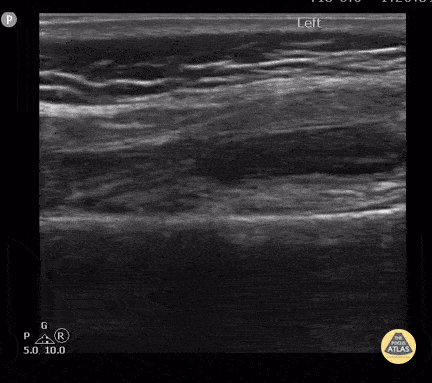

17 month old with knee effusion due to septic arthritis. Knee radiography was normal. Note the distal femur, physic and epiphysis seen on the lower part of the screen below the effusion and the hypoechoic non-ossified patella cartilage typically seen in this age. Contributor: Antonio Riera, MD, Yale University School of Medicine